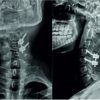

A right-handed 18-year-old male patient reported to the outpatient orthopedic department with swelling over the distal phalanx of his left-hand little finger that was steadily expanding and producing clubbing during a 6-month period. Swelling was linked to pain, which was worse at night and relieved with NSAIDs. Physical examination revealed localized edema with clubbing of the distal region of the left little finger, as well as an expanded nail plate and a disturbed nail fold angle. On comparing to the contralateral hand, the movement range at the distal interphalangeal joint was found to be normal. Before surgery, the patient had a visual analog scale (VAS) score of 8 (Figs. 1 and 2).

His blood investigations revealed no rheumatic and inflammatory illnesses, and he ruled out any history of trauma or infection. Radiographs indicated a lytic lesion of the right index finger’s distal phalanx with surrounding sclerosis (Figs. 3 and 4), for which magnetic resonance imaging was performed, which revealed a well-defined eccentric mildly expansile intracortical lesion involving the lateral cortex of the diaphysis of the distal phalanx of the little finger, with a central hypointense sclerotic area within surrounded by diffuse marrow edema (Figs. 5 and 6) giving differential diagnosis of